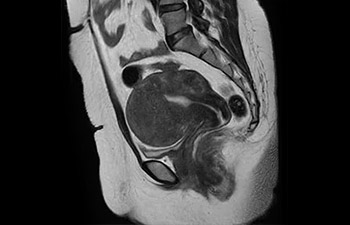

Bekken vrouw met myoom

met Compressed SENSE